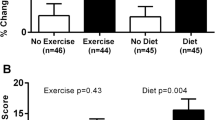

In the pilot REDHART trial, 60 patients with recently decompensated HFrEF were randomly assigned 1:1:1 to anakinra for 2 weeks, anakinra for 12 weeks, or placebo [23]. No significant differences in peak VO2 were seen with anakinra, or placebo, at 2 weeks. At 4 and 12 weeks, the patients treated with anakinra for 12 weeks showed an improvement in peak VO2 compared with baseline, whereas those treated with anakinra for 2 weeks or those treated with placebo did not improve peak VO2 [41]. In this trial, we expect that the increased sample size and prolonged treatment duration of the REHDART2 trial will provide sufficient power for an assessment of the treatment effect of IL-1 blockade on peak VO2. Furthermore, the REDHART2 trial will also employ a more stringent definition for “reduced” ejection fraction (LVEF ≤ 40%) as compared with the original pilot REDHART trial (LVEF ≤ 50%).

In the large multicenter CANTOS trial, treatment with canakinumab, IL-1β blocking antibody, reduced HF-related adverse events in patients with prior MI [20]. In a small single-center sub-study of the CANTOS trial in 15 patients with pre-existing HFrEF, canakinumab significantly increased peak VO2 at 3 months compared to placebo (median interval change of + 1.6 [from − 0.4 to + 3.4] mL kg−1 min−1; P = 0.026 between group changes) [40].